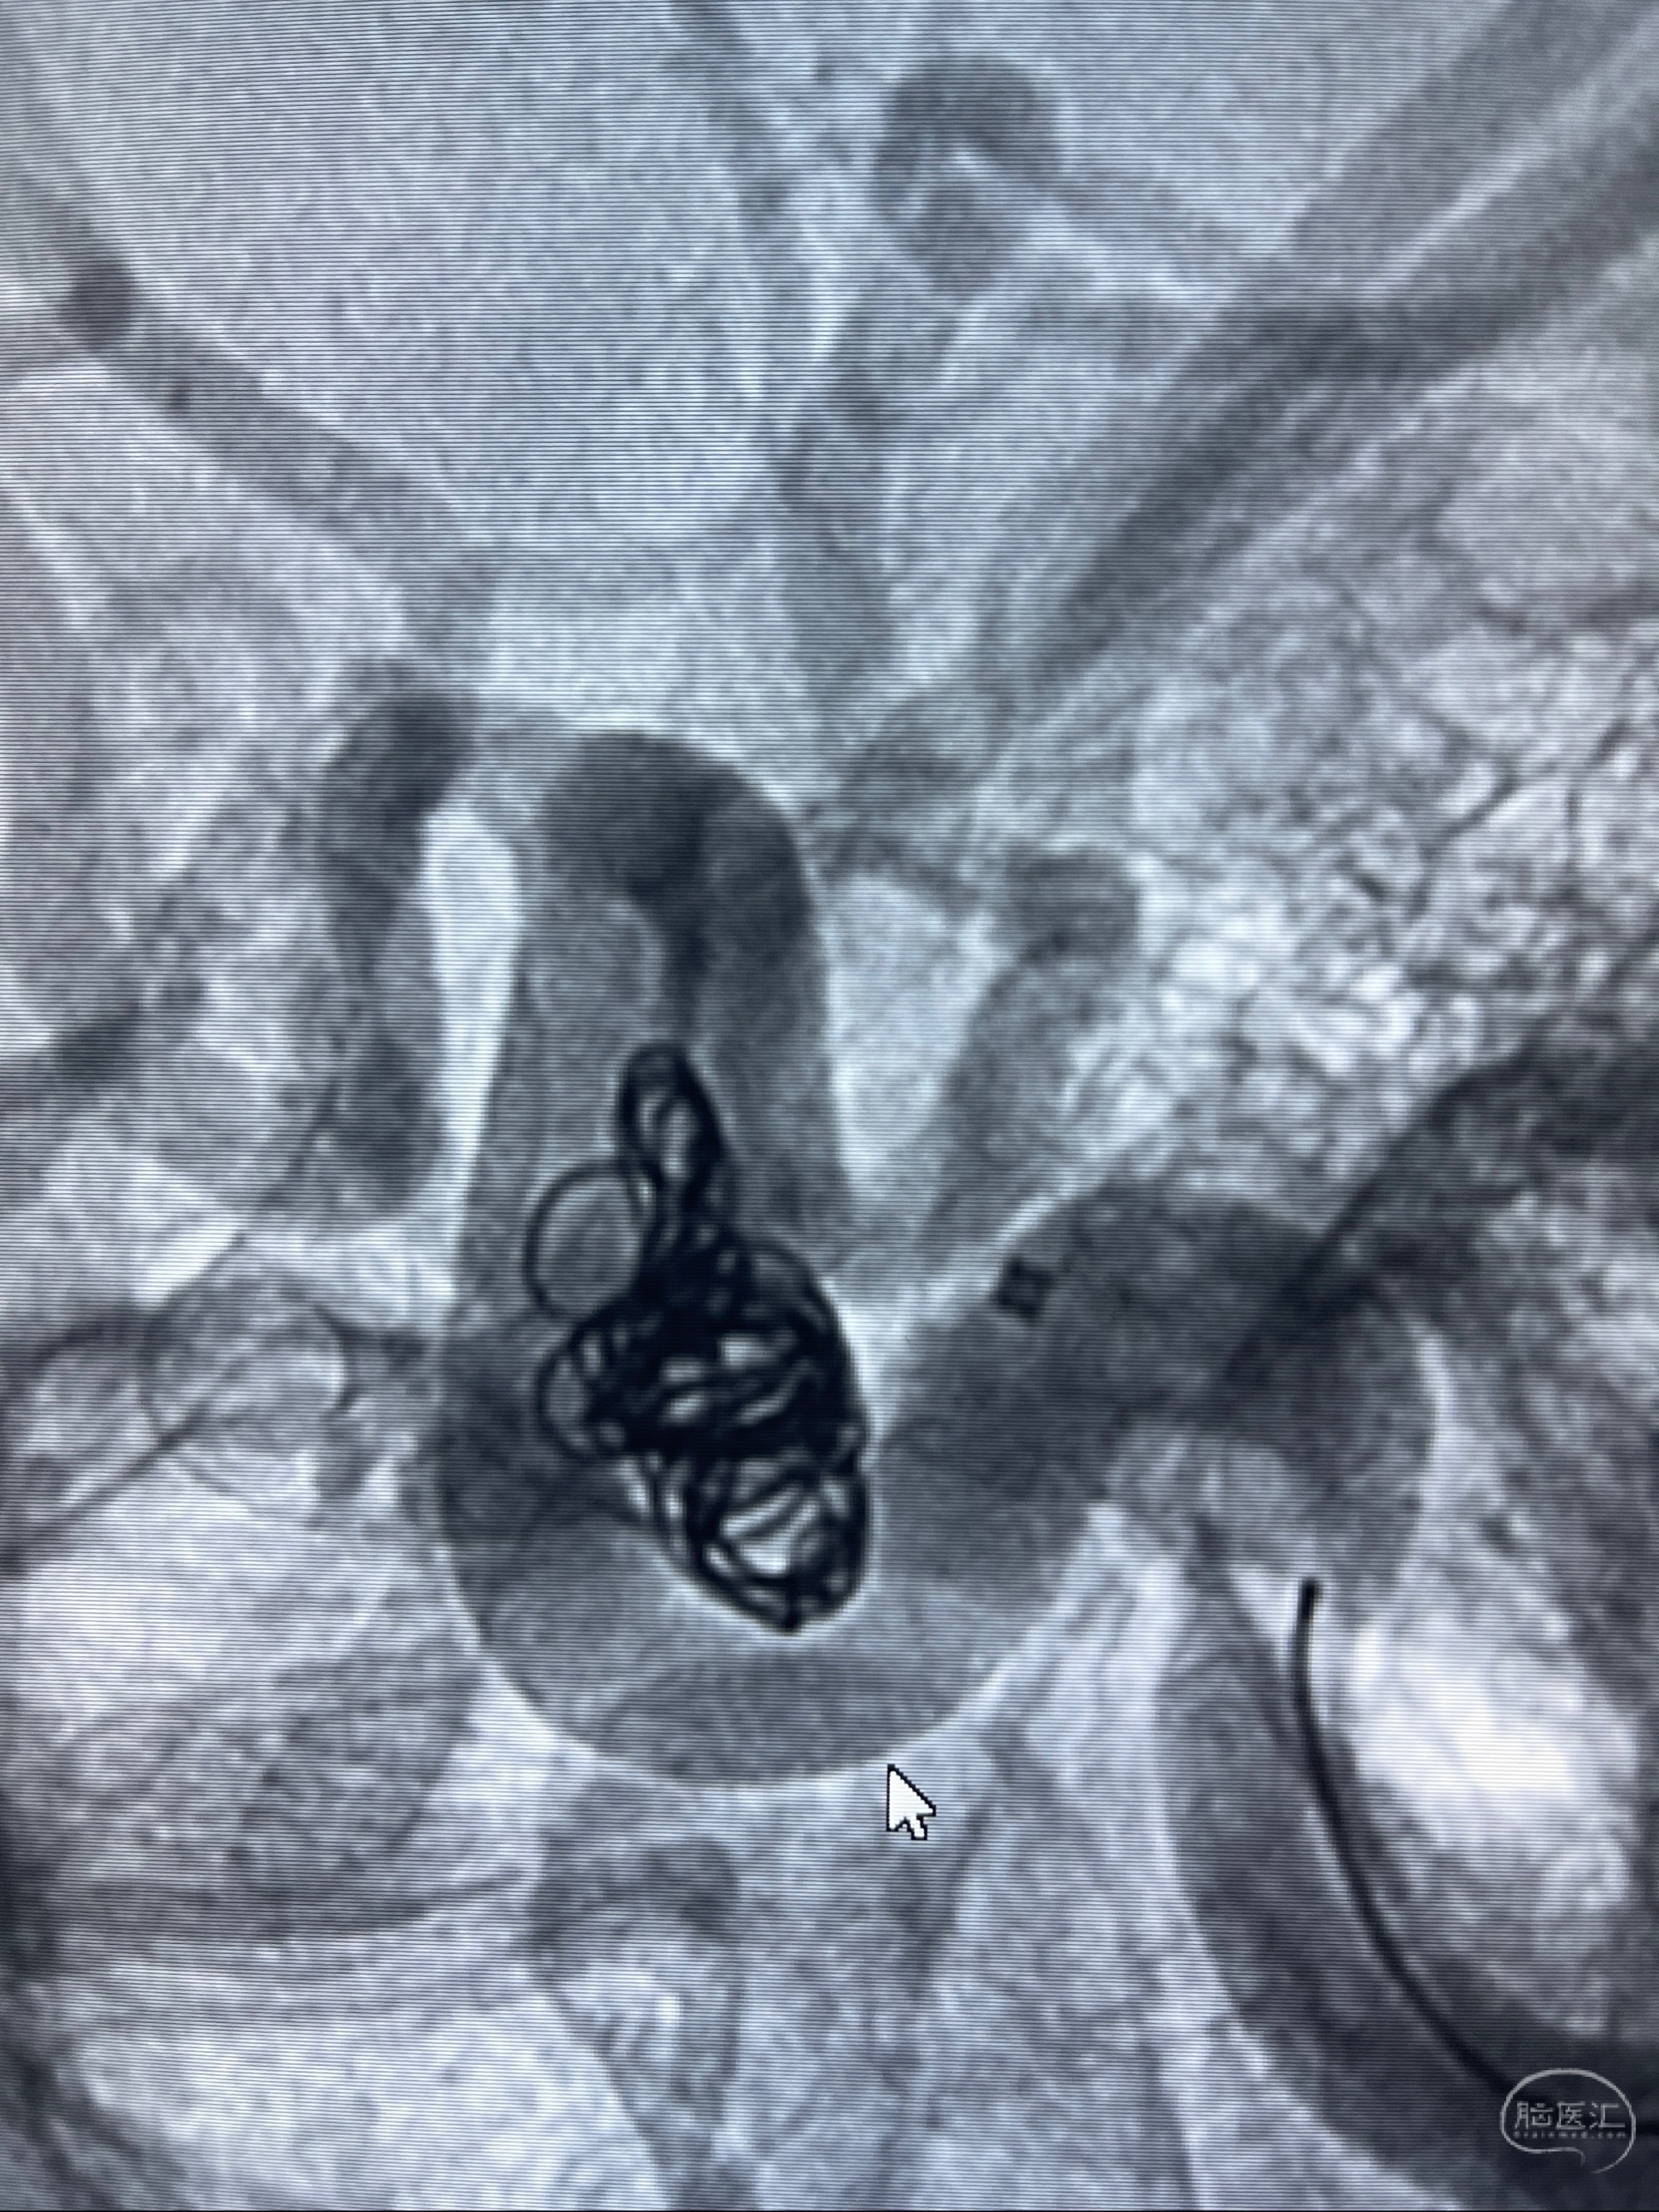

2023-07-27全脑血管造影:双侧颈内动脉眼动脉段动脉瘤,右侧较大

2023-08-01全麻下行双侧颈眼动脉瘤支架辅助栓塞

- pipeling4.5-20mm

- pipeline 4.0-20mm

术后即刻CT